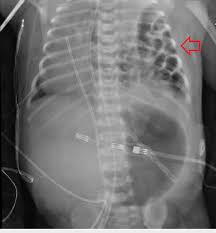

선천 횡격막 탈장 (Congenital diaphragmatic hernia)

• Bochdalek hernia: left posterolateral hernia (m/c)

• 임상 양상

• 청색증, 빈호흡, 흉골함몰 등이 생후 수시간 내 발생

• scaphoid abdomen

• 이환된 쪽 호흡음 소실

• 진단: 흉부 X선 검사

Chest X-ray of the congenital diaphragmatic hernia (arrow ...